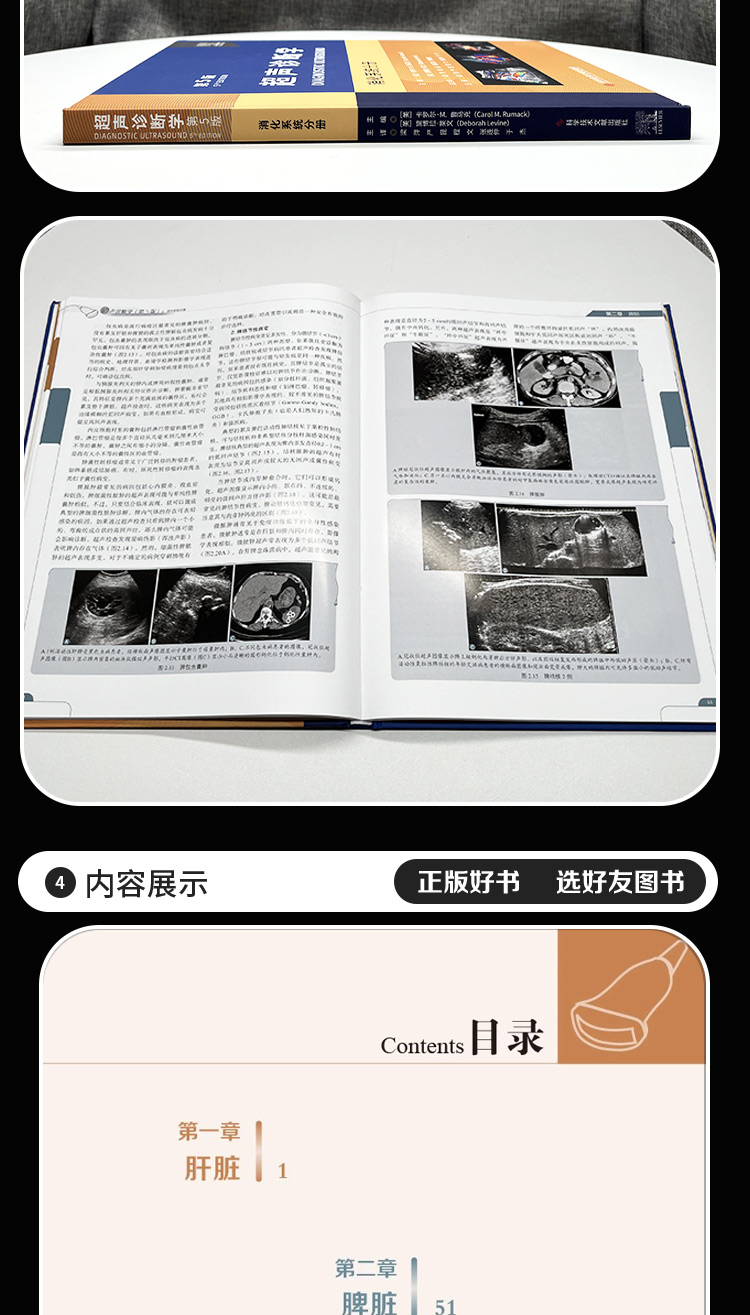

内容提要:

内容提要: